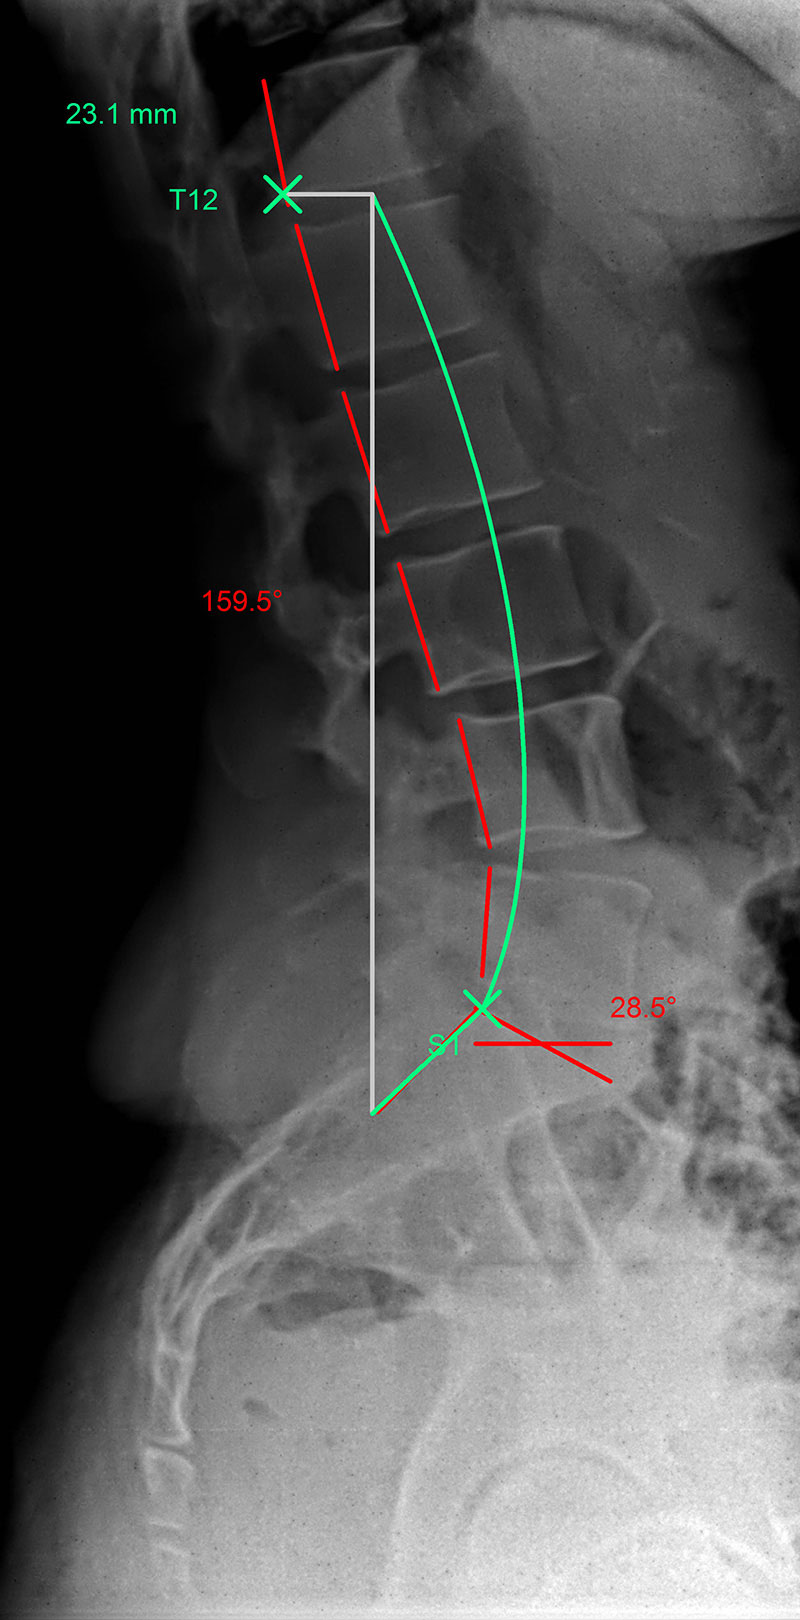

Hyperlordosis: |

The green line represents the ideal spinal curvature and the red line that of the patient’s spine in profile view.